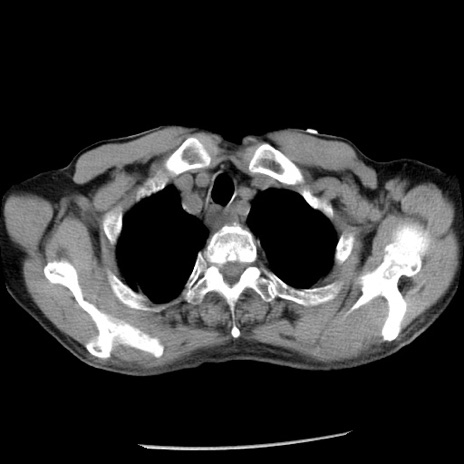

冠状断像